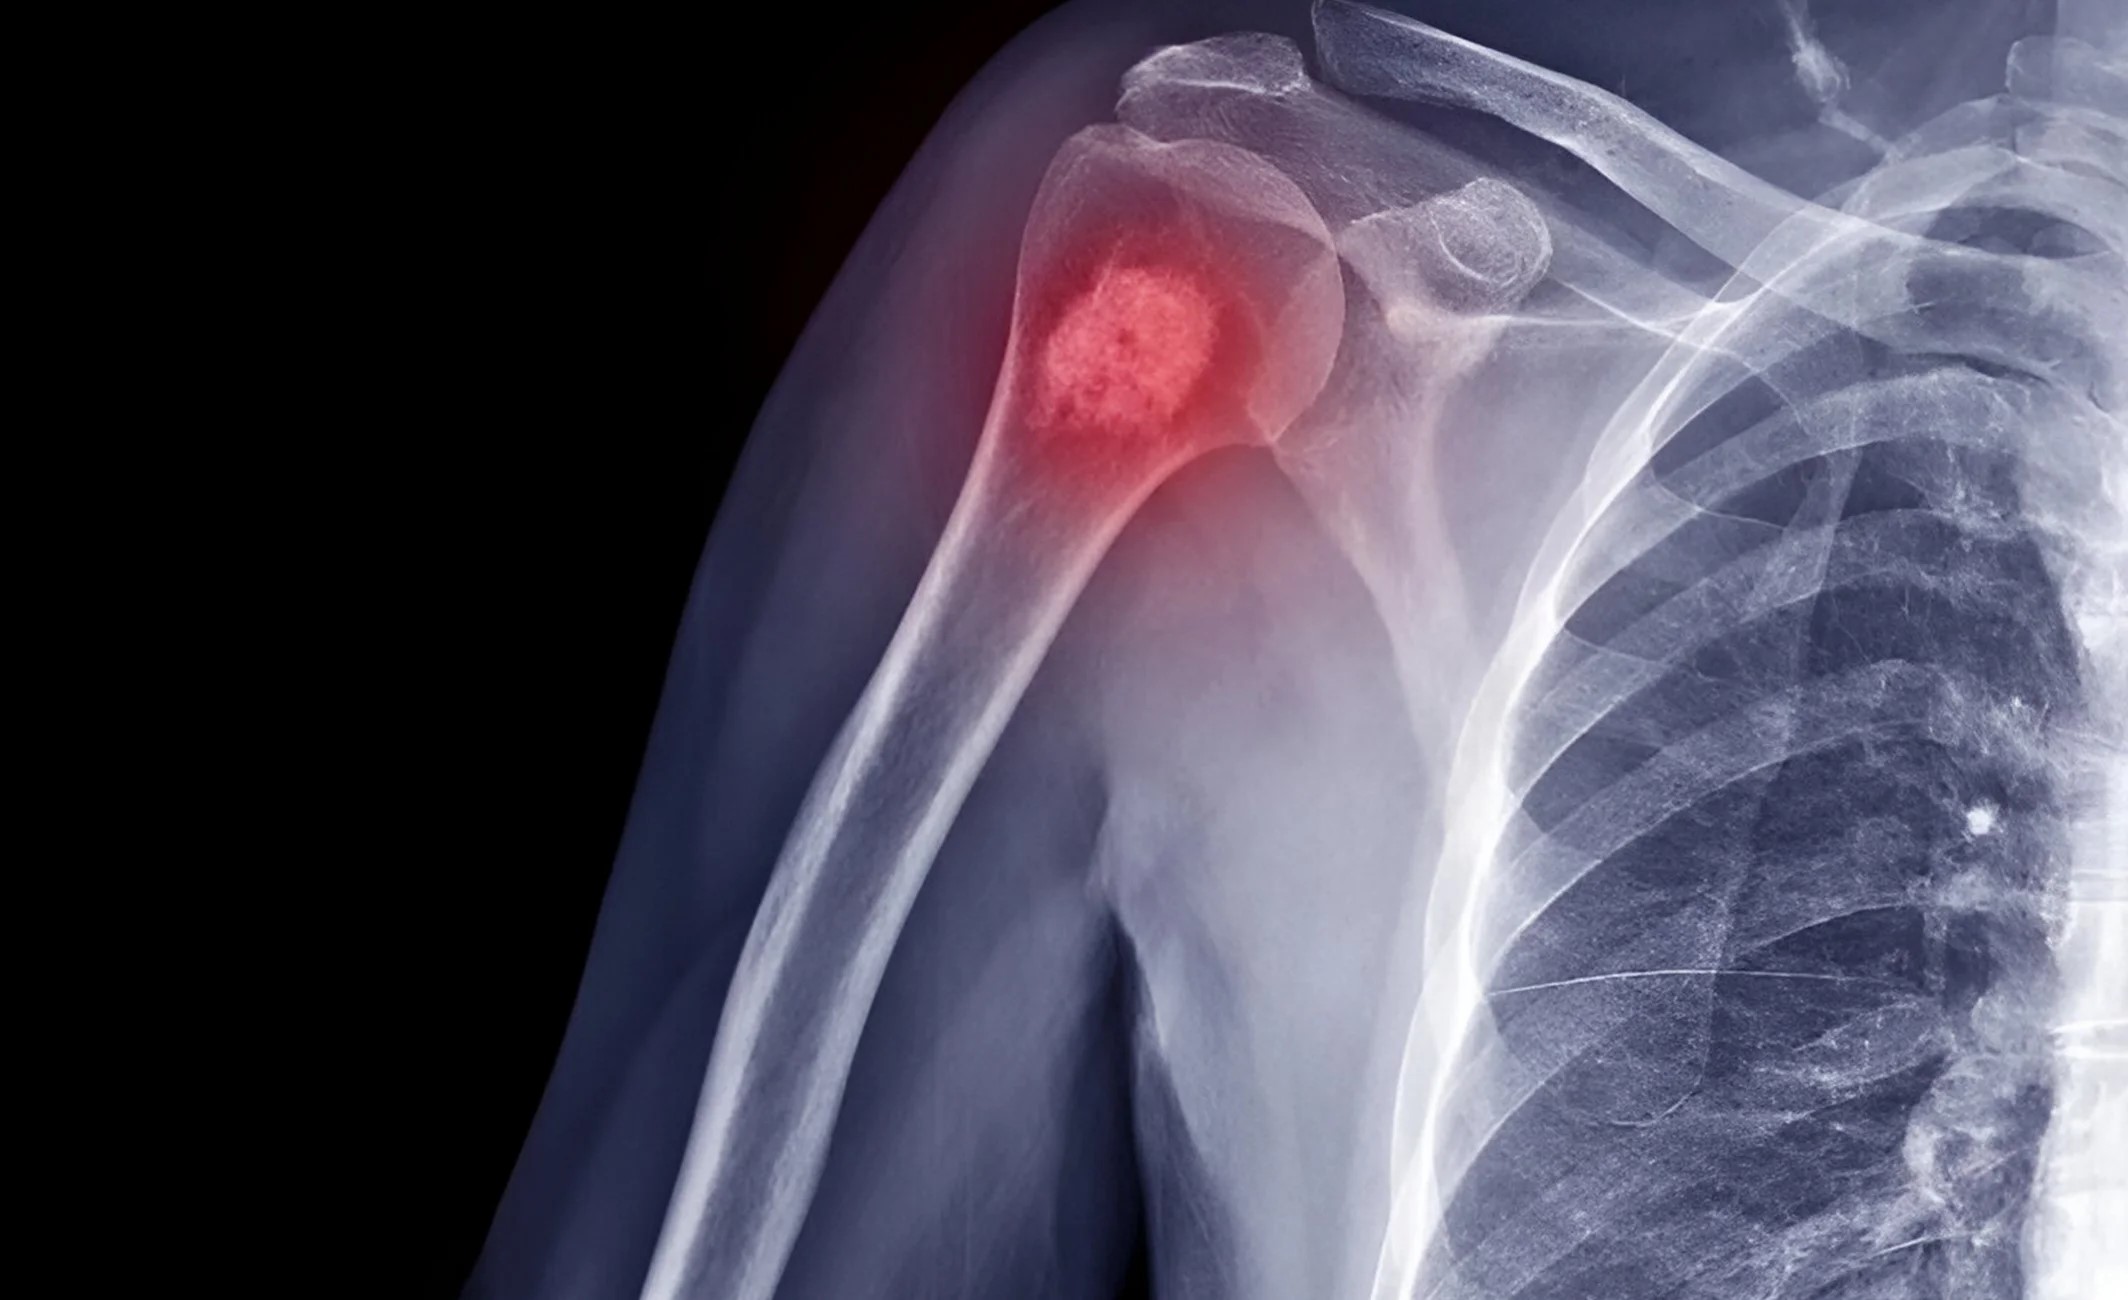

ان خیالات کا اظہار جناح اسپتال کے ماہر امراض ہڈی و جوڑ ڈاکٹر سجاد بگھیو نے نجی ٹی وی سے گفتگو کے دوران کیا، انہوں نے کہا کہ میں ہڈیوں اور نرم ٹشوز کے ٹیومرز کے بارے میں بات کرنا چاہتا ہوں، جنہیں مسکیولو اسکیلیٹل ٹیومرز کہا جاتا ہے۔

انہوں نے کہا کہ ان میں ہڈی، پٹھوں، چربی اور دیگر نرم ٹشوز کے کینسر شامل ہوتے ہیں، لیکن بدقسمتی سے لوگ اکثر انہیں نظرانداز کردیتے ہیں۔ اگر ہاتھ، پیر یا ٹانگ میں ایسی سوجن ہو جو مسلسل بڑھتی رہے، ایک ماہ سے زیادہ برقرار رہے یا سوجن ہو مگر درد نہ ہو، تو یہ خطرے کی علامت ہوسکتی ہے۔

اسی طرح ہڈیوں میں ایسا درد جو خاص طور پر رات کے وقت زیادہ ہو یا عام درد کی دواؤں سے ٹھیک نہ ہو، تشویش ناک ہوسکتا ہے۔

انہوں نے کہا کہ اگر معمولی چوٹ لگنے سے ہڈی ٹوٹ جائے تو یہ بھی اس بات کی علامت ہوسکتی ہے کہ ہڈی میں پہلے سے کوئی بیماری یا کینسر موجود ہے۔ ایسی علامات کو سنجیدگی سے لینا چاہیے اور فوری ماہر آرتھوپیڈک یا آنکولوجی سرجن سے رجوع کرنا چاہیے، نہ کہ دیسی علاج پر انحصار کیا جائے۔

انہوں نے کہا کہ پاکستان میں ہمارے پاس ان کیسز کے ماہر ڈاکٹرز کی کمی ہے، لیکن پھر بھی تمام ڈاکٹرز کو پیغام دیتا ہوں کہ اگر ذرا بھی شک ہو تو بائیوپسی سے پہلے کوئی علاج نہیں ہونا چاہیے اور بائیوپسی سے پہلے کیس کی پوری تحقیق ہونی چاہیے، ہمیں شک ہوتا ہے تو سب سے پہلے ایکسرے اور ایم آر اے سمیت دیگر ٹیسٹ اور بائیوپسی کرواتے ہیں۔ یہ سب مراحل کے بعد ہم علاج کی جانب بڑھتے ہیں، جس سے ہمیں بیماری کی موجودگی اور شدت کا اندازہ ہوتا ہے۔

مزید برآں شدید کیسز میں پہلے ہم کیموتھراپی اور ریڈیو تھراپی سے بیماری کو سُکھیڑ دیتے ہیں اور اس کے بعد ہم مریض کی سرجری کرتے ہیں، گوشت اور پٹھوں کے ٹیومر بالغ میں عام ہیں، یہ اکثر بغیر درد کے ہوتے ہیں جبھی ان پر توجہ نہیں دی جاتی، لیکن گوشت اور پٹھوں کے ٹیومرز میں سوجن ظاہر ہونے لگ جاتی ہے جب کہ بچوں میں ہڈیوں کے ٹیومرز زیادہ ہوتے ہیں، جن میں وہ درد کی شکایت بھی کرتے ہیں۔